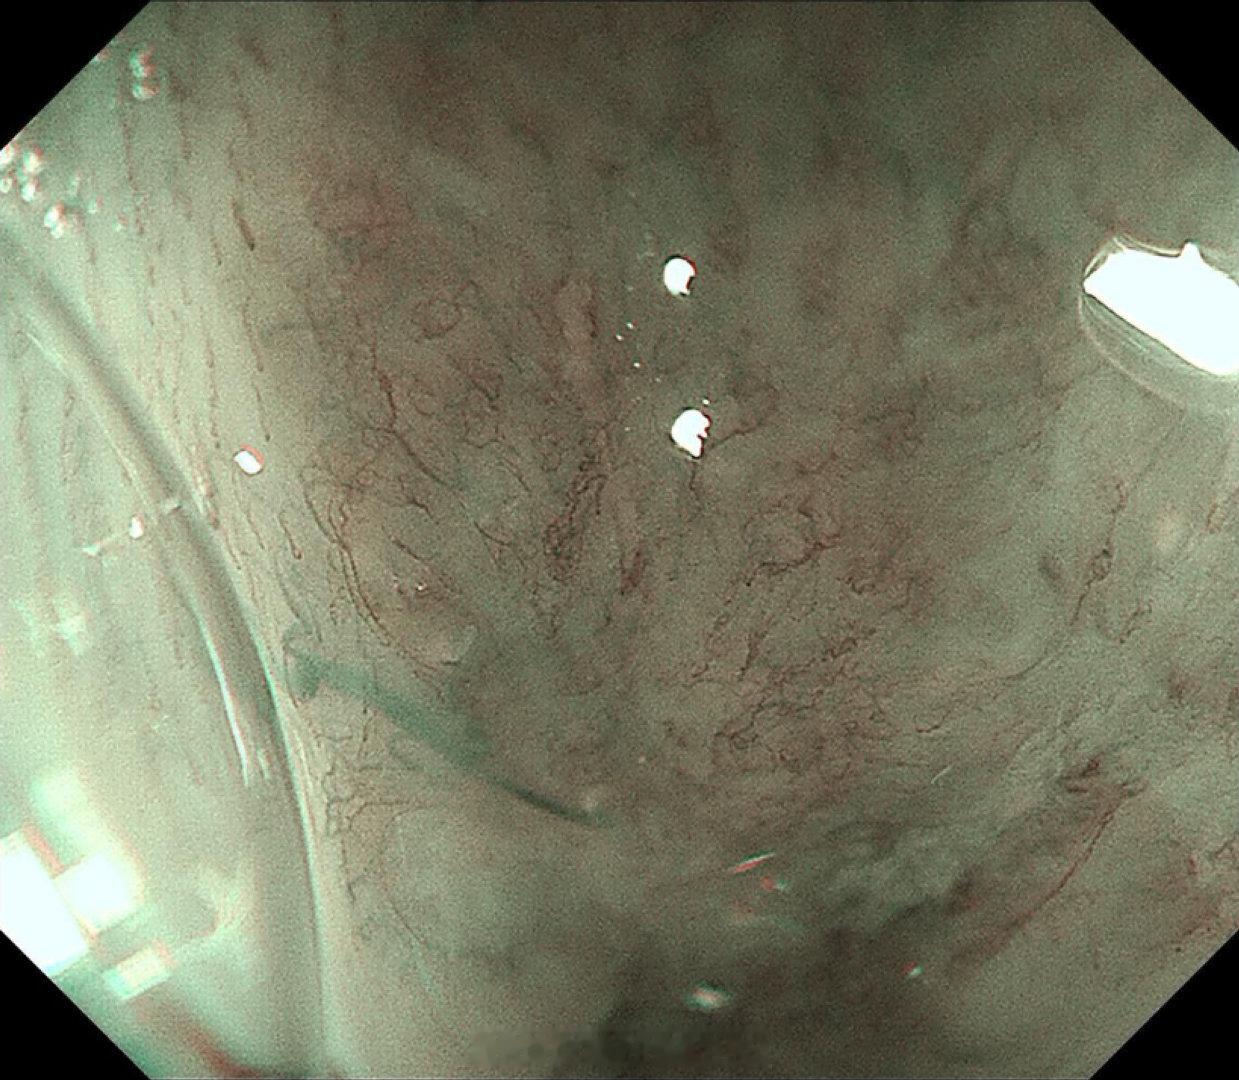

这是个兄弟医院做的内镜发现有贲门病灶,老人体型腹型肥胖很典型,返流持续那么多年导致的Barrett食管癌风险肯定是最高的,她女婿找我精查会诊了一次,我看着病灶虽小,但是有点僵硬,感觉已经到了黏膜下的barrett食管癌,但是他们都想尝试切除看看浸润深度,诊断性esd实施后黏膜下550微米,一般来说这地方超过500微米已经是sm2,淋巴结转移风险急剧加大了,后面就要纠结要不要追加外科手术,但是这个手术做了生活质量会相当不好。所以这种癌的最好措施是预防,发现非常困难,往往一发现就是深了。腹型肥胖的人群减重以减少返流是很重要的。